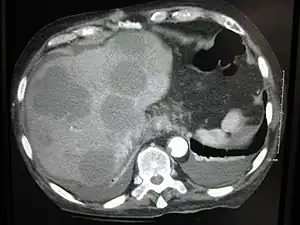

- Liver metastasis: hepatomegaly (enlarged liver), nausea[9] and jaundice[9]

Metastatic tumors are very common in the late stages of cancer. The spread of metastasis may occur via the blood or the lymphatics or through both routes. The most common sites of metastases are the lungs, liver, brain, and the bones.[10]

This is typical route of metastasis for sarcomas, but it is also the favored route for certain types of carcinoma, such as renal cell carcinoma originating in the kidney and follicular carcinomas of the thyroid. Because of their thinner walls, veins are more frequently invaded than are arteries, and metastasis tends to follow the pattern of venous flow. That is, hematogenous spread often follows distinct patterns depending on the location of the primary tumor. For example, colorectal cancer spreads primarily through the portal vein to the liver.